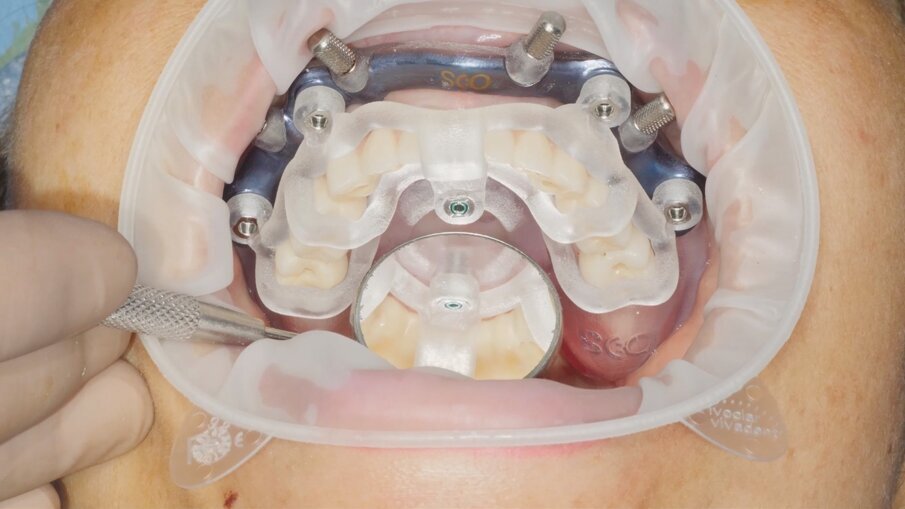

La programmazione della fase chirurgica viene svolta in collaborazione con ODS – Oxy Digital Solutions e prevede l’impiego di un sistema di dime componibili sviluppato per garantire il trasferimento preciso delle informazioni dal progetto virtuale al paziente reale. Il sistema – chiamato Pcube – osserva l’applicazione di una dima base che rappresenta il punto di riferimento per tutte le procedure riabilitative del caso in analisi (Fig. 8). Il posizionamento della dima base, contraddistinta dell’unione funzionale di materiali da stampa 3D e titanio fresato, avviene mediante l’utilizzo di un indice di posizionamento a sua volta avvitato sulla dima base stessa attraverso un sistema di microviti che guiderà le successive apposizioni di dima implantare e carrier della protesi. L’indice di posizionamento è l’esatta copia della protesi definitiva e riprende le analisi dimensionali e occlusali svolte in fase di pianificazione.

Una volta posizionata la dima base mediante pin di fissaggio e rimosso l’indice di posizionamento, sugli stessi alloggiamenti avvitati viene posizionata la dima chirurgica per il posizionamento implantare. Questa componente è realizzata totalmente in titanio fresato e coniuga leggerezza, resistenza e ampia accessibilità chirurgica. La protesi può contare su un rinforzo in fibra di vetro continuo (Hi fiber – Moi Dental), una scelta che assicura solidità al manufatto e, grazie alla sua trasparenza e fluorescenza, caratteristiche estetiche che i materiali di rinforzo tradizionali non riescono a garantire. La protesi viene posizionata sulla dima base mediante un carrier avvitato sugli stessi alloggiamenti precedentemente utilizzati per l’indice di posizionamento e per la dima implantare.

Fase chirurgica Entrando nel vivo delle fasi chirurgiche, vediamo in Fig. 9 l’alloggiamento dell’indice di posizionamento per il fissaggio della dima base. È molto importante effettuare un primo try-in prima dell’anestesia così da accertare il corretto alloggiamento della protesi su tessuti privi di gonfiore. Dopo l’anestesia si procede a verificare nuovamente la posizione andando a comprimere le zone dove può essersi accumulato liquido anestetico. Verifichiamo il corretto alloggiamento del sistema Pcube attraverso le finestre di ispezione e verificando l’intercuspidazione con l’arcata antagonista. Rimosso l’indice di posizionamento (Fig. 10) possiamo apprezzare l’ampio accesso al campo chirurgico offerto dalla dima base e procedere con la fase di scansione intraoperatoria (Trios 4 – 3Shape). Abbiamo infatti deciso per fini documentali di procedere a una serie di scansioni per verificare in modo continuativo l’effettivo grado di precisione del trattamento rispetto alla pianificazione digitale grazie alla sovrapposizione dei file .stl (Fig. 11). Procediamo quindi con il fissaggio della dima chirurgica in titanio anodizzato, sempre sfruttando i sistemi di ancoraggio della dima base (Fig. 12). L’utilizzo di un mucotomo è il passaggio preliminare alla preparazione del sito implantare, non prevedendo, in questo caso, l’apertura di un lembo. Questa scelta si lega alla buona disponibilità ossea e di tessuto cheratinizzato della paziente; tuttavia, la finestra di accesso al campo operatorio garantita dalla dima base del sistema Pcube permette approcci a lembo aperto senza prevederne la rimozione (Fig. 13).